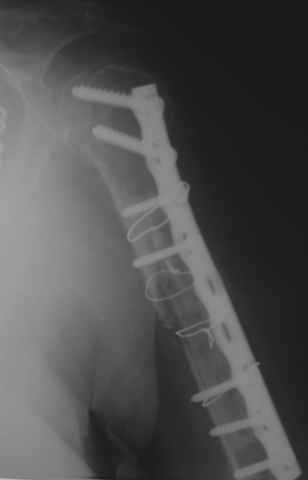

Уважаемые коллеги! На консультации больная 65 лет. С одной рентгенограммой - рис.1.

Анамнез: 30 августа перелом левой плечевой кости, невропатия лучевого нерва - кисть повисла сразу. Лечение по месту жительства - иммобилизация косынкой. 2 октября в одной из больниц города металлоостеосинтез. Все развалилось. 16 октября - повторная операция, через десять дней - картина на рис.1. Далее металлоостеосинтез с костной аутопластикой малоберцовой костью 9 февраля 2009г. Снимки 2-4 выполнены сегодня.

Считаем, что шансов на приживление и перестройку такого трансплантата в данной ситуации нет. Нестабильность запрограммирована и вываливание этого всего дело ближайшего будущего. Вопросы для обсуждения:

1. Кто-нибудь считает, что надо оставить "как есть"? Аргументы?

2. Если оперировать, то что выбрать:

- фиксация пластиной с угловой стабильностью с ревизией нерва;

- блокированный остеосинтез;

3. Что делать с трансплантатом

- удалить

- измельчить и оставить

- не трогать, попытаться "нанизать" на гвоздь закрыто.